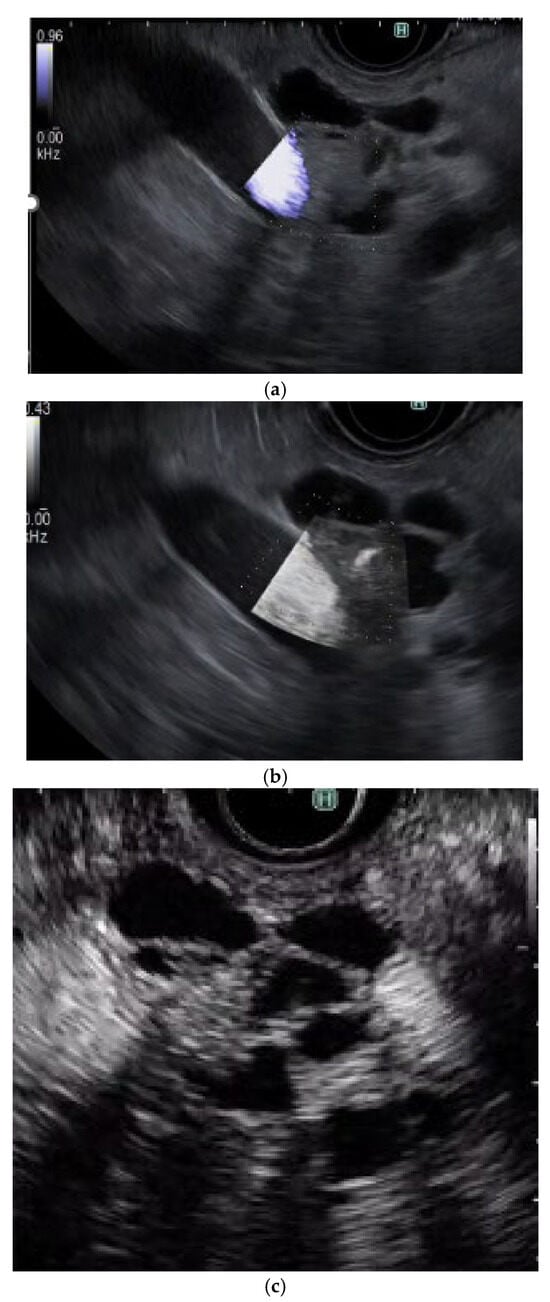

(C)

DFI-EUS

DFI-EUS (32/33 cases, 97%) is significantly superior to e-FLOW EUS (24/33 cases, 73%) for differential diagnosis between mural nodules and mucous clots in IPMN and between solid gallbladder lesions and gallbladder sludge (Figure 7) [44]. Although no clear conclusion can be drawn due to including gallbladder disease in this study, DFI-EUS is expected to be a useful tool for differential diagnosis between mural nodules and mucous clots in IPMN and will likely replace CH-EUS in the future.

Figure 7. The sensitivity of vascularity for detecting a mural nodule in IPMN using each modality. (a) e-Flow EUS: No vessels are detected in the mural nodule. (b) DFI-EUS: Detected a vessel in the mural nodule. (c) CH-EUS: Detected a mural nodule with vascularity.